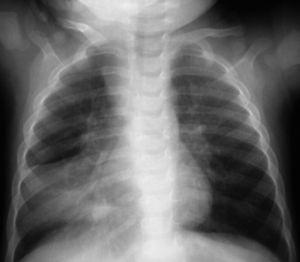

A los niños con Mantoux positivo se les realizó una radiografía de tórax que fue patológica en 10 de los 11 (90,9 %) que fueron derivados a nuestro hospital. El niño sin alteraciones radiológicas recibió profilaxis con isoniazida durante 9 meses. La edad media fue de 23,1 meses (11-42 meses). De estos 10 niños, siete estaban sintomáticos en el momento del estudio, cinco presentaban tos, cinco fiebre y uno eritema nudoso (tabla 1). Las imágenes radiológicas mostraron condensación parenquimatosa en el 90 % de los pacientes y adenopatía parahiliar en el 50 % (figs. 1-3).

Figura 1. Paciente n.º 8. Atelectasia del lóbulo medio e inferior derecho.

Figura 2. Paciente n.º 1 (evolución). Atelectasia del lóbulo inferior derecho.

Figura 3. Paciente n.º 1 (inicial). Condensación del lóbulo medio derecho.

Los 10 pacientes con radiografía patológica iniciaron el tratamiento con isoniazida, rifampicina y pirazinamida. Siete pacientes presentaron una buena evolución no precisando otros tratamientos ni exámenes complementarios. Sin embargo, en 3 niños se observaron alteraciones de la ventilación en la radiografía de tórax en forma de atelectasia al inicio del tratamiento. En estos niños se practicó una broncoscopia y se añadieron corticoides al tratamiento tuberculostático. Los 3 niños tuvieron buena evolución. Al finalizar el tratamiento de 6 meses, todos los niños estaban asintomáticos y con normalización de las imágenes radiológicas. La estancia media en el hospital fue de 5 días. No se detectaron casos de tuberculosis en los miembros de la familia de los niños enfermos.

En pacientes pediátricos, la presencia de linfadenopatía hiliar, mediastínica o cervical, afección pulmonar con infiltrados segmentarios o lobulares, neumonía consolidada, atelectasias, derrame pleural o tuberculosis miliar representan el espectro de enfermedad en este grupo de población 32. En nuestros casos la forma de presentación más frecuente fue la consolidación pulmonar seguida de adenopatías hiliares y atelectasia pulmonar.

Las lesiones pulmonares tuberculosas se encuentran con mayor frecuencia en el pulmón derecho (55 %). En nuestro estudio, de los niños que presentaban imágenes de condensación parenquimatosa, cuatro se localizaron en el pulmón derecho y cinco en el izquierdo. De preferencia las lesiones se localizan en las porciones mejor ventiladas, parte baja del lóbulo pulmonar superior y alta del inferior. Muy raras veces en el vértice. En la mayoría de los casos, el foco es único, raras veces doble 33.